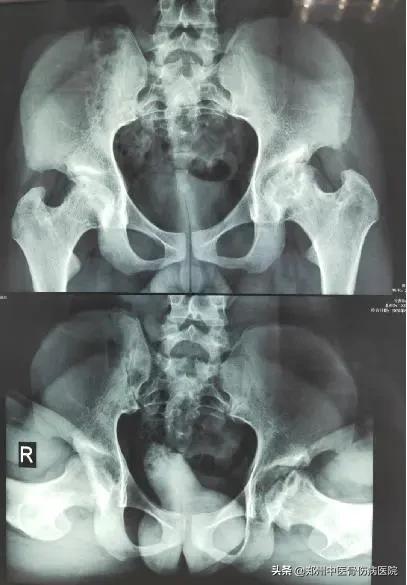

发生在髋关节的剥脱性骨软骨炎:

聂先生,男,19岁,河南新乡人。主诉:双髋间断性疼痛4年6个月。2015年7月到延津县某医院摄双髋CT:双侧股骨头缺血性坏死可能性大。2018年08月第1次住院治疗。

自诉双髋疼痛不重,查体功能活动尚可。舌质红,苔薄黄。脉滑数。患者个子不高,智力正常。

腰椎椎体呈“*弹子**头”样改变。双侧腹股沟中点无压痛,双髋关节活动尚可,双“4”字试验阳性,下蹲可。

家族中无类似疾病发生。经服药治疗3年余,缺损的骨质得到新生骨质的填充,患者弃拐行走。